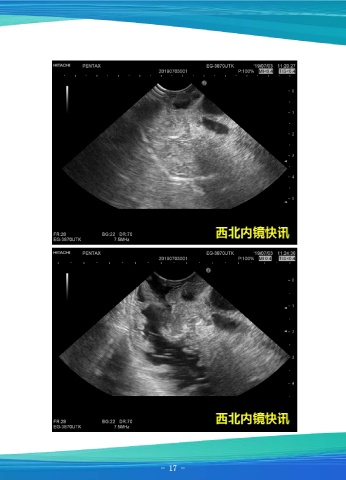

超声胃镜示:见胆总管明显扩张,最宽25mm,腔内未见异常,向下追踪,见胰管

最宽5.6mm,胆胰管汇合处管壁明显增厚,延伸至乳头,呈低回声改变,乳头增大,截

面直径14.7x6.6mm,换用十二指肠镜观察见乳头表面增生不平,血管呈树枝状改变,

活检质软。活检病理提示:十二指肠乳头局灶癌变。患者在全麻下行胰十二指肠根治性

切除术,手术顺利。